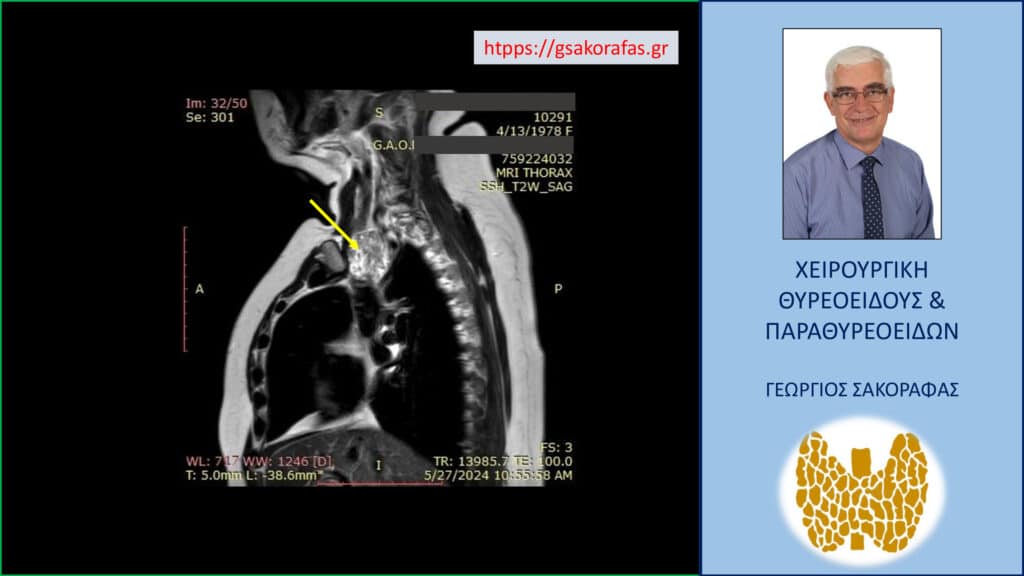

Σε επιλεγμένους ασθενείς μπορεί να χρειαστεί να γίνει αξονική ή μαγνητική τομογραφία, όπως για παράδειγμα όταν υπάρχει κατάδυση στο μεσοθωράκιο για την αξιολόγηση του βάθους στο οποίο εκτείνεται μέσα στον θώρακα η βρογχοκήλη.